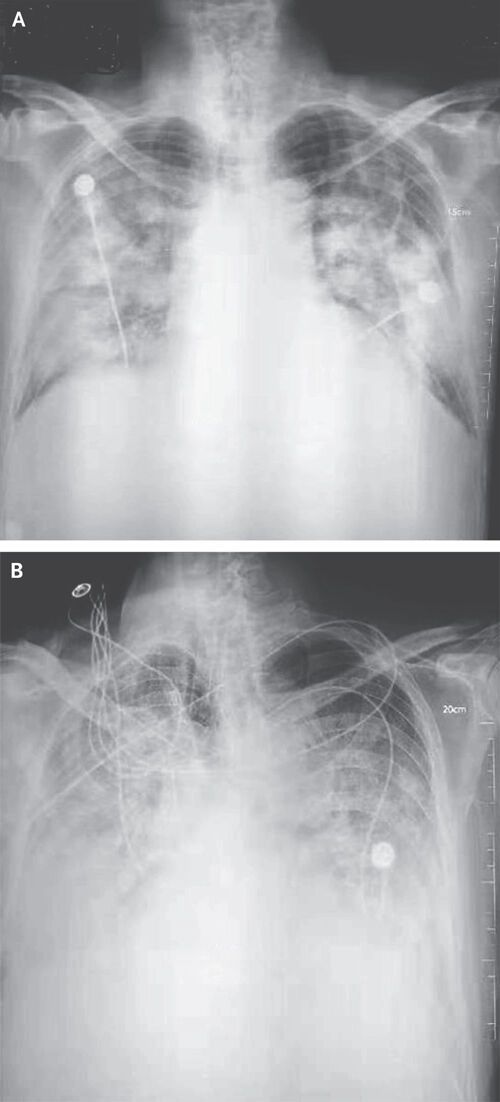

▲ 우한 폐렴 환자의 흉부 방사선 사진

환자가 병원에서 일반적인 방식(후전위 또는 전후위 자세)으로 가슴 X선 촬영을 하면, AI 알고리즘이 이 영상을 분석해 폐에 이상 소견이 있는지, 있다면 어느 위치에 있는지를 의료진에게 알려줍니다.

AI가 검출할 수 있는 이상 소견은 ▲ 결절(폐에 생긴 작은 혹) ▲ 경화(폐 조직 일부가 딱딱하게 굳는 현상) ▲ 간질성 음영(폐 조직 사이의 공간에 이상이 생겨 X선 영상에서 비정상적으로 보이는 부분) ▲ 흉막삼출(폐를 둘러싼 막 사이 공간에 물이 차는 현상) ▲ 기흉(폐에 구멍이 생겨 공기가 새어 나오는 상태) 등 5가지 주요 질환입니다.

(사진=NEJM 논문 발췌, 연합뉴스)